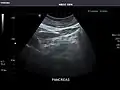

Pancreas: Visualized portions unremarkable.

Pancreas